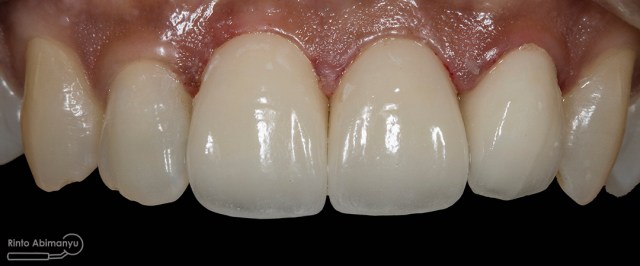

Foto klinis setelah pemasangan crown

Alhamdulillah pasien nya senang sekali…. dia puas dan saya pun senang karena dapat memenuhi keinginan pasien…..

Nah ini resume foto before dan after perawatannya…